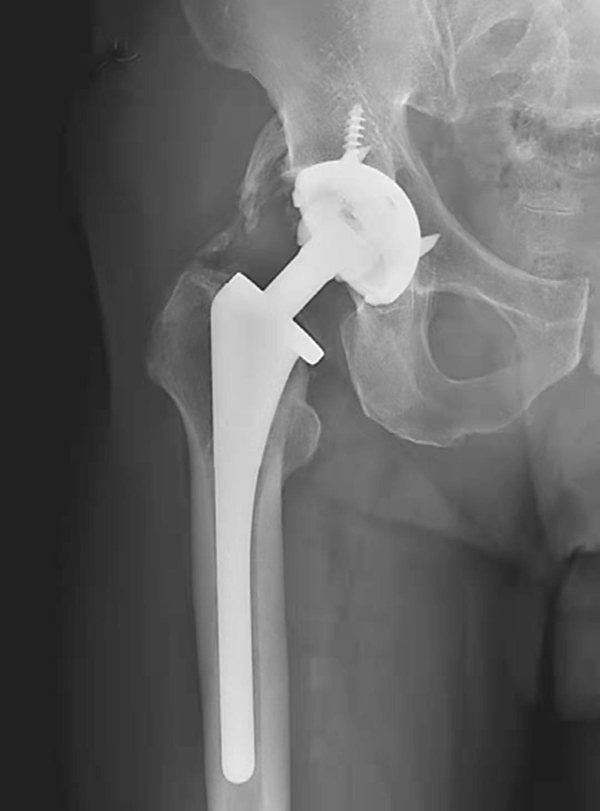

图6 右侧人工髋关节置换术后异位骨化

平片,右侧人工髋关节外方可见条片状骨化影

图7 右侧人工髋关节置换术后异位骨化

平片,右侧人工髋关节外上方可见条片状骨化影

图8 右侧人工髋关节置换术后异位骨化

平片,示右侧人工髋关节内下方见条片状骨化影